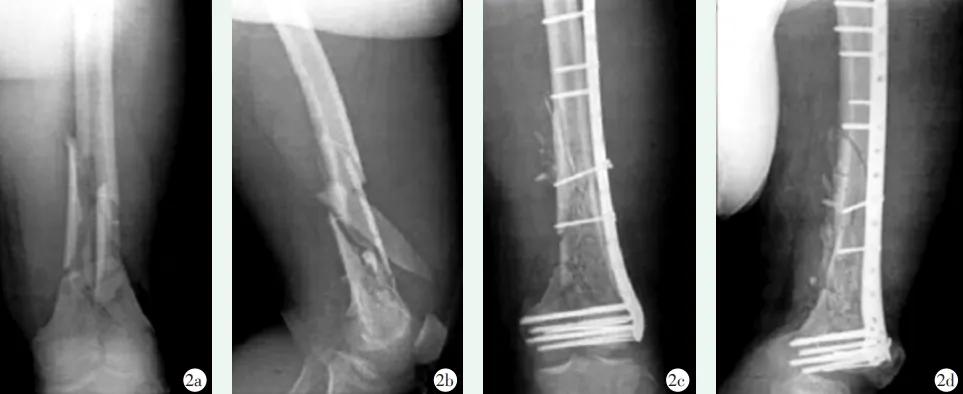

图4 患者,男,37岁,车祸导致左侧股骨远端C3型骨折,采用解剖锁定钢板内固定治疗 2a,2b:术前正侧位X线片示左侧股骨远端C3型骨折 2c,2d:术后复查X线片示内固定稳定,复位良好。